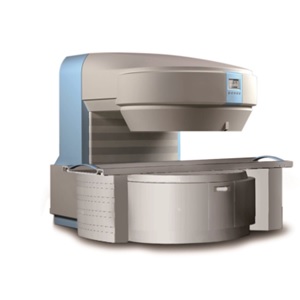

Description

MAGNETIC RESONANCE IMAGING SYSTEM

MRI 0.35T